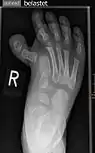

.jpg.webp)

يُلاحظ تزوّي (ميلان) الإصبع لاتجاه خارج مركز الجسم من بعد المفصل.

أروح (valgus) وأفحج (varus) مصطلحان خاصان بالتزوِّي (angulation) في الجزء البعيد من أحد الأطراف عند المفصل، أي ميلان الجزء البعيد عند المفصل إما للخارج (أروح) أو للداخل (أفحج). ومنهما التصريف اللغوى: فحجي، فحجاء، وكذلك: روح، روحي، روحاء. هناك تزوّي (ميلان) طبيعي بعد المفصل كمثال: الكوع، حيث لا يكون الساعد على استقامة واحدة مع العضد بعد الكوع، ولكن الساعد يتزوّى للخارج بمقدار 5-10° درجات في الحالة الطبيعية.

تَشَوُّهٌ أَرْوَح

(Valgus deformity).

يُلاحظ تزوّي (ميلان) الساق للخارج بعد مفصل الركبة.